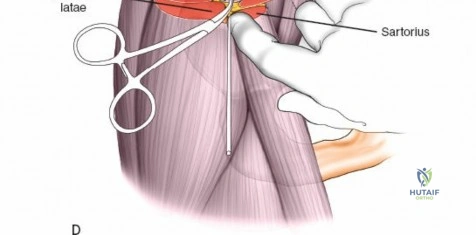

Wrist and Metacarpal Safe Zones

For spanning wrist fixators, distal pins are placed in the second metacarpal. The safe zone is the dorsoradial aspect of the second metacarpal base and shaft. The first dorsal interosseous muscle and extensor tendons must be respected. The radial artery courses proximally in the anatomic snuffbox and must be avoided during basal metacarpal pin insertion.

Metacarpal Pin Placement

1. Make two 1 cm incisions over the dorsoradial aspect of the second metacarpal.

2. Dissect bluntly, protecting the dorsal sensory branches of the radial nerve and the extensor tendons.

3. Place the tissue sleeve at a 45-degree angle to the dorsal and lateral planes to maximize purchase in the metacarpal shaft.

4. Pre-drill and insert two 3.0 mm pins.